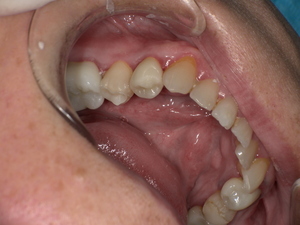

After: セラミックで修復され、天然歯のように自然な白さと透明感がある美しい歯の状態。どこが治療箇所か分からないほど自然な白さへ。

年齢・性別: 50代男性

治療期間: 約2週間(通院2回)

費用総額: 93,500円(税込)